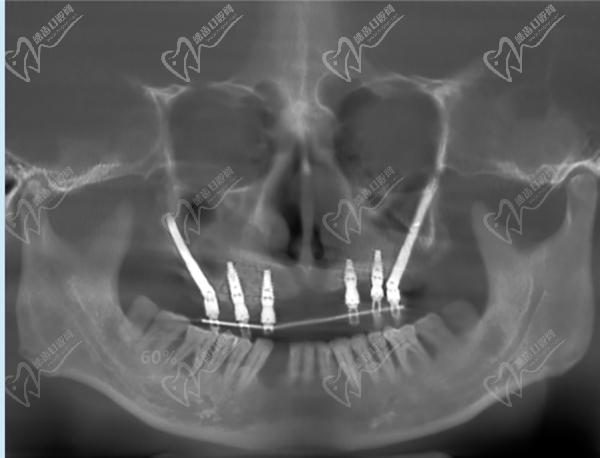

7、廣州暨博口腔醫(yī)院(體育東店):專注口腔醫(yī)療20余年,在牙齒美白、全口種植等方面技術嫻熟。

廣州柏德口腔主打德系口腔,引進德國先 進的口腔診療設備和技術。 注重數(shù)字化技術應用,提供更可靠的診療服務。 擁有一批經(jīng)驗豐厚的醫(yī)生團隊,擅長處理各種復雜的口腔問題。注重3D數(shù)字化種植技術,術前種植牙方案模擬和設計更準。也側重數(shù)字化正畸技術,矯正過程更精 準高 效。